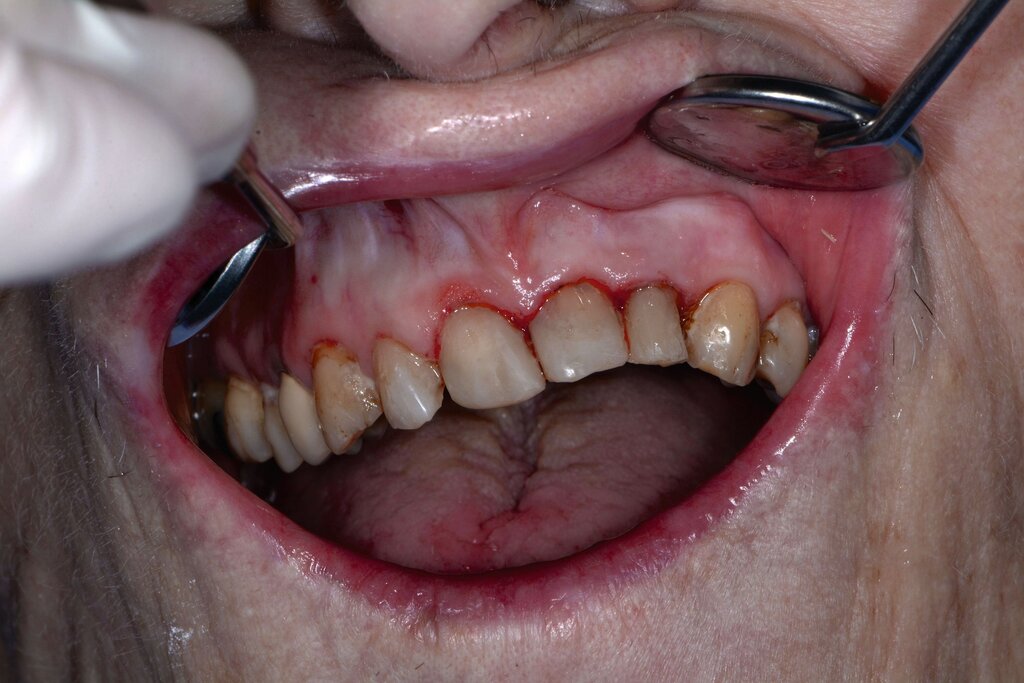

Auch wenn sich Karies, Parodontitis und dentale Traumata bei dieser vulnerablen Hochrisikogruppe in absehbarer Zeit wohl nicht gänzlich vermeiden lassen, ermöglicht die regelmäßige zahnmedizinische Kontrolluntersuchung, dass einzelne Befunde frühzeitig identifiziert und mit moderatem Aufwand therapiert werden können (Abbildung 5). Bei stark reduzierter Therapiefähigkeit sollten als Minimalziel die oralen Strukturen schmerz- und entzündungsfrei sein, um lebensbedrohliche Komplikationen wie Pneumonien oder Bakteriämien zu verhindern. Parodontale und periimplantäre Erkrankungen sollten im Kontext des allgemeinen Gesundheitszustands, der physiologischen Alterung des Immunsystems und der allgemeinen Körperfunktion beurteilt werden [Paris et al., 2020; Müller et al., 2022]. Prothetische Rehabilitationen sind zum Erhalt der Kaufunktion und der mundgesundheitsbezogenen Lebensqualität je nach Lokalisation und Ausmaß des Zahnverlusts sinnvoll, bedingen aber ein Mindestmaß an Mitarbeit von Patient und betreuendem Umfeld. Eine möglicherweise reduzierte Adaptationsfähigkeit an neu angefertigten Zahnersatz gilt es besonders bei neurodegenerativen Erkrankungen im Vorfeld der Therapie zu besprechen [Nitschke et al., 2021].